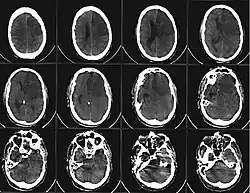

Aus der oben beschriebenen Problematik ergibt sich die Dringlichkeit der raschen ärztlichen Evaluation zur potenziellen Indikation einer Lysetherapie, deren wirksames Zeitfenster allgemein als 4,5 Stunden nach Symptomeintritt angesehen wird. Auch innerhalb dieses Zeitfensters für die Anwendung von Maßnahmen, welche geeignet sind die Blutversorgung wiederherzustellen, hat sich gezeigt, dass zur Minimierung bleibender Schäden ein frühestmöglicher Therapiebeginn angestrebt werden sollte. In der Darstellung fast aller Schlaganfall-Formen haben sich moderne MRT-Geräte mit spezialisierten, perfusions-diffusions-gewichteten und anderen spezialisierten Sequenzen (FLAIR, T2*) als überlegen erwiesen, aufgrund der häufig jedoch schlechteren Verfügbarkeit bei längerer Untersuchungsdauer ist die Notfalldiagnostik bei entsprender Anamnese und klinischem Bild nach wie vor häufig das CCT. Dieses eignet sich prinzipiell zum schnellen Ausschluss der primären Kontraindikationen der Lysetherapie mit RtPA, dem Vorliegen einer intracraniellen Blutung sowie eines Hirntumors. Besonders bei unklarem Symptombeginn ist das MRT jedoch in der Lage, durch Bestimmung eines Perfusions-Diffusions-Mismatchs, also die Darstellung eines Areals, über dem die perfusionsgewichtete Bildgebung schon auffällig, die diffusionsgewichtete jedoch noch nicht auffällig ist, einen Eindruck des schon geschädigten in Relation zum noch zu schädigenden Areal (Penumbra) zu geben.[10]